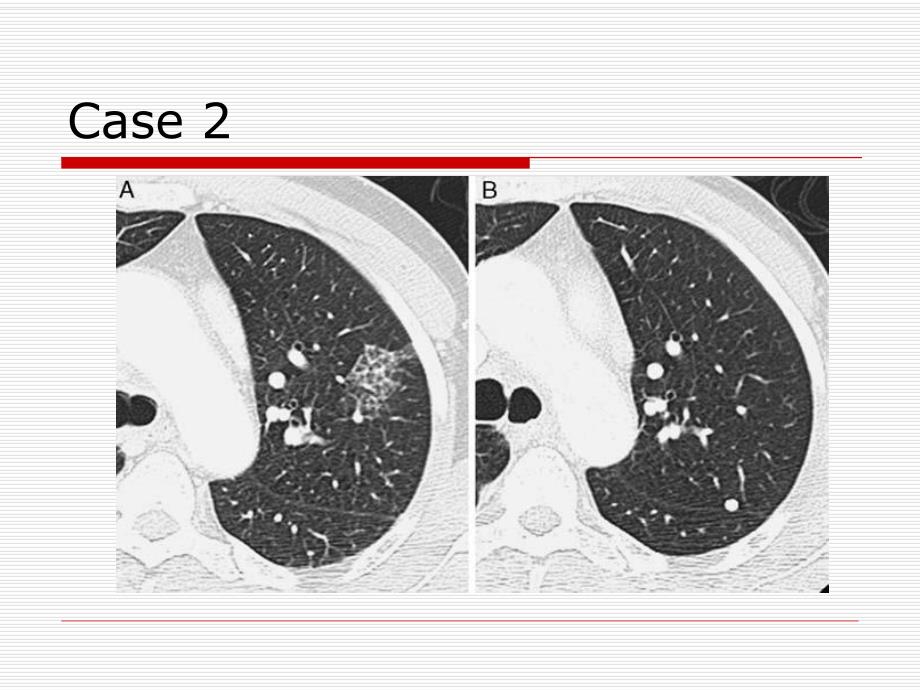

1、肺结节肺结节CT随访策略随访策略Case 1o 女,66岁o pGGNCase 2Case 3肺结节(pulmonary nodule)o 定义:指肺实质内单发或多发的圆形或类圆形、直径3 cm,不伴有肺不张、无淋巴结肿大或肺内其他异常的病变分类o 纯磨玻璃密度(pGGN,pGGO)o 混合性结节(partial solid GGN)o 实性结节(Solid Nodule)实性结节实性结节无肺癌危险因素排除吸烟史;年龄60岁;有肺癌史或肺外其他癌病史o 4mm,无须随访,但患者必须完全知情随访的利与弊o 4 mm-6 mm,隔12个月随访1次,若无变化无需随访o 6 mm-8 mm,612、1

4、描技术o 高分辨o 低剂量(80mA)o 薄层(2.5mm)良性结节男,39岁;a-GGN,b-3个月后随访肺腺癌女,59岁;a-GGN,b-5个月后随访,c-9个月后随访;有卵巢癌病史。肺癌新分类与CT特征相关性不典型腺瘤样增生(AAH)o 5mmo 部分实性结节:71%o 实性结节o pGGN:7%腺癌o 女,66岁o(a)pGGN o(b)2 年后 随访 o(c)CT引导楔形切除粘液腺癌(Invasive mucinous adenocarcinomas)o 实性结节o 实性为主结节o 分叶o 多发(BAC)CASEo 女,57岁o AISo A:CTo B:18月后o C:PET(-)

5、CASEo 男,66岁o A:左肺上叶pGGNo B:2年后随访CTo 病理:鳞状上皮腺癌CASEo 女,70岁o 鳞状上皮腺癌o 图示每年一次随访平均倍增时间o pGGN:813天o 部分实性结节:457天o 实性结节:149天参考文献参考文献oCHEST 2013;143(5)(Suppl):e93Se120S Diagnosis and Management of Lung Cancer,3rd ed:American College of Chest Physicians Evidence-Based Clinical Practice GuidelinesoCurr Opin Pul